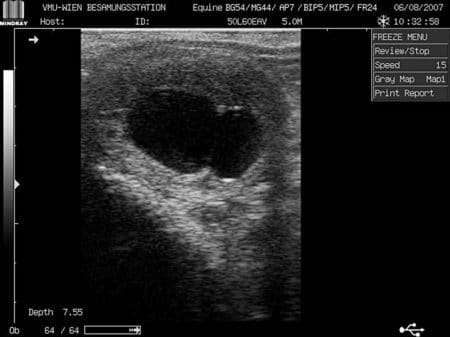

- Untersuchung zwischen Tag 14 und 18 nach dem Eisprung: Die klinische Trächtigkeitsdiagnostik erfolgt direkt, das heißt mit Hilfe einer transrektalen Ultraschalluntersuchung. Diese kann im Stall oder in der Klinik stattfinden. Sofern kein Untersuchungsstand, in dem die Stute von einem Brustgurt fixiert untergebracht ist, zur Verfügung steht, gibt es alternative Maßnahmen (z. B. Aufheben eines Vorderhufes, Sedierung bei nervösen Tieren, etc.), die eine gefahrlose Untersuchung ermöglichen. Während der Untersuchung wird ein linearer 5- oder 7,5-MHz-Rektalschallkopf eingesetzt. In diesem frühen Zustand der Trächtigkeit untersucht der Tierarzt die gesamte Gebärmutter (Uterus) vom inneren Muttermund bis zu den Hornspitzen und Eierstöcken mindestens zweimal. Die Trächtigkeitsuntersuchung sollte nicht zu früh erfolgen. Bereits ab dem zehnten Tag ist die Frucht ultrasonographisch darstellbar, bis Tag 18 kommt es aber immer noch zu Trächtigkeitsverlusten. Die Ultraschalluntersuchung schadet der Trächtigkeit aber nicht und führt selbst nicht zu Fruchtverlusten. Etwa bis Tag 15 ist die Frucht in der Gebärmutter beweglich und kann sich daher an jeder Stelle des Uterus befinden, ab Tag 16 ist sie an der Basis eines Uterushornes fixiert. Die transrektale ultrasonographische Diagnostik liefert ab dem 14. Tag mit 97 Prozent sehr zuverlässige Ergebnisse. Auch die Qualität der Fruchtanlage lässt sich ultrasonographisch beurteilen. Hier spielt das Wachstum und ab dem 22. Tag die Darstellung der Herzaktion eine wichtige Rolle. Dabei kann festgestellt werden, ob die Herzfrequenz des Embryos vorhanden ist. Falls nicht, muss der Tierarzt nach einer Wartezeit von 24 Stunden einen Abbruch der Trächtigkeit einleiten. Die Ovarien der Stute gehören auch zu den zu untersuchenden Organen, da diese einen oder mehrere Gelbkörper bilden können, was wiederum eine Zwillingsträchtigkeit anzeigen könnte.

- Untersuchung je nach Vorgeschichte der Stute ab Tag 24 und 27: Ab diesen Zeitpunkt sind Fruchtwasser, Embryo und dessen Herzaktionen sichtbar.

- Untersuchung zwischen dem 30. und 40. Tag Nun kann der Tierarzt eine Trächtigkeit bestätigen. Der 33. Tag ist der letztmögliche Termin, eine Zwillingsträchtigkeit relativ risikofrei, das heißt ohne den Zyklus zu stören (Azyklie), abzubrechen. Nach dem 40. Tag der Frühgravidität sind bis Ende des fünften Monats zunächst keine weiteren ultrasonographischen Trächtigkeitsuntersuchungen erforderlich. Erst ab dem sechsten Monat sollte eine weitere rektale und ultrasonographische Untersuchung auf dem Programm stehen. Bei Stuten mit bekannter Neigung zu Aborten sind auch wiederholte Untersuchungen zu empfehlen. Anzeichen für eine gestörte Gravidität sind eine verdickte Uteruswand, die sich teigig anfühlt, und wenig Fruchtwasser. Um Fetus und Plazenta deutlicher zu sehen, eignet sich die sogenannte transabdominale Ultrasonographie. Dies ist eine Untersuchung mit Ultraschall durch die Bauchdecke der Mutter hindurch. Hierfür reicht es, das Fell gut mit Alkohol zu befeuchten und auf den Ultraschallkopf ausreichend Gel aufzutragen. Der Tierarzt benutzt für diese Untersuchung im Zeitraum vom 80. bis 160. Trächtigkeitstag ein anderes Ultraschallgerät, nämlich das Real-Time B-Mode Gerät mit 5 MHz-Schallkopf, und für Stadien darüber hinaus einen 3,5-MHz-Schallkopf. Um die Uteruswand und Plazenta darstellen zu können, sind höhere Ultraschallfrequenzen erforderlich. Um die Herzaktionen des Fetus zu messen, reichen hingegen niedrigere Frequenzen von 2,5 MHz.